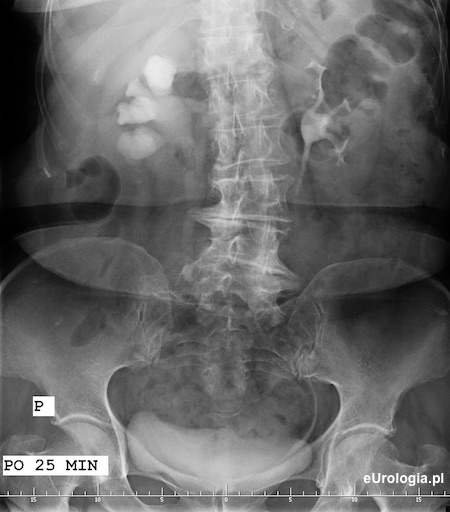

Wodonerczowo poszerzony UKM prawej nerki i poszerzony górny odcinek moczowodu aż do opisywanego na zdjęciu przeglądowym cienia - złóg w moczowodzie.

Zółtą strzałką oznaczono cień wapienny o wymiarach 11x8 mm będący złogiem w górnym odcinku prawego moczowodu.